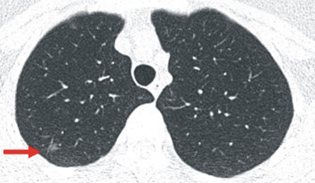

蕭小姐的低劑量胸部電腦斷層影像發現肺部右上肺陰影(紅色箭頭所指)